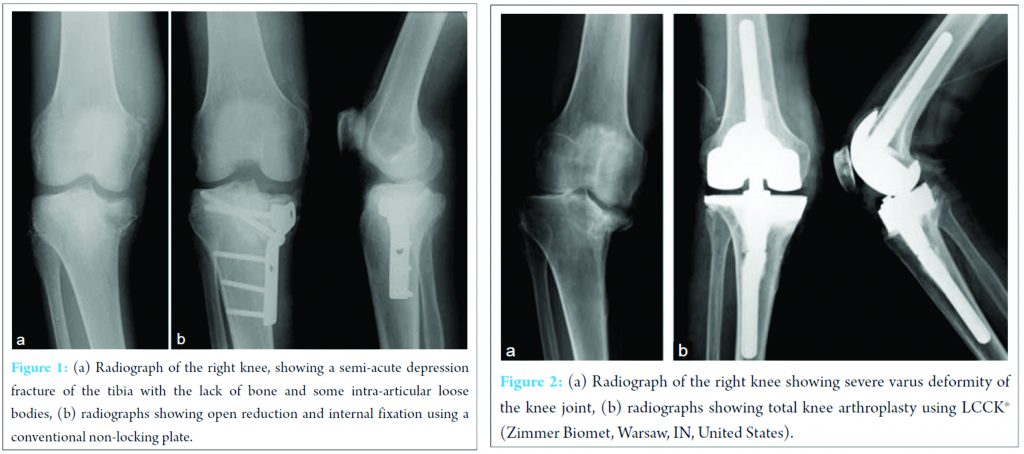

A 63-year-old man with syphilis and a body mass index of 19.6 kg/m2 presented with a painful swollen knee 1 month after slipping. Radiographs revealed a semi-acute depression fracture of the tibia with comparatively large defect of bone and some intra-articular loose bodies considering the pain. He had deep tendon hyporeflexia, hypo pallesthesia, disturbance of deep sensibility, and decreased protective sensation due to tabes dorsalis. Therefore, his right knee was diagnosed as a Charcot joint disease. Open reduction and internal fixation (ORIF) using a conventional non-locking plate was performed (Fig. 1). Varus deformity and delayed bone union gradually developed after the procedure. At this point, his clinical depression worsened and was accompanied by abnormal behavior. The results of the blood test TPLA 6600 (TLHA 5120 X) had deteriorated to TPLA 22000 (TPHA 10240 X). Tabes dorsalis had been treated with antibiotics (ampicillin). Despite the treatment, the patient had to be transferred to a psychiatric hospital because of aggravated neurologic manifestations. He was diagnosed with organic mental disorder caused by tabes dorsalis and was hospitalized for 2 months. 1 year later, ORIF metal removal was performed.

About 10 years after the first knee symptoms, the patient visited our hospital because of right knee pain and an abnormal gait. Clinical examination showed severe varus deformity and limitation of the range of motion. TKA was carried out with LCCK® (Zimmer Biomet, Warsaw, IN, United States) (Fig. 2). The pain subsequently subsided and the patient had an improved range of motion in the knee.4 weeks after the surgery, the patient experienced a slight pain in his right heel while walking. Radiographs did not reveal any obvious fractures (Fig. 3a). After a 1-week period of observation, plain radiographs showed an avulsion calcaneal fracture (Fig. 3b). This right calcaneus fracture was successfully treated with ORIF using two cannulated cancellous screws and a cerclage wire (Fig. 4a, b, c). 3 weeks after the surgery, partial weight bearing was permitted with a vacuum-stabilized orthosis (VACOped®, OPED, Oberlaindern, Germany) that allowed for angle adjustments at five-degree intervals. Full weight-bearing was allowed at 7 weeks after surgery. The surgical wounds healed without complications. 6 months after ORIF, bone union was eventually achieved and metal removal was performed. At the final follow-up, the patient was able to walk without difficulty. There has been no early loosening of the prosthesis so far.